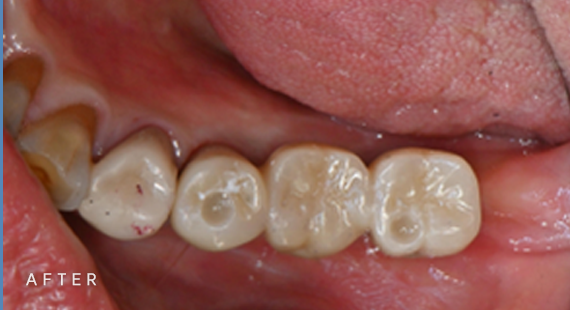

충치치료